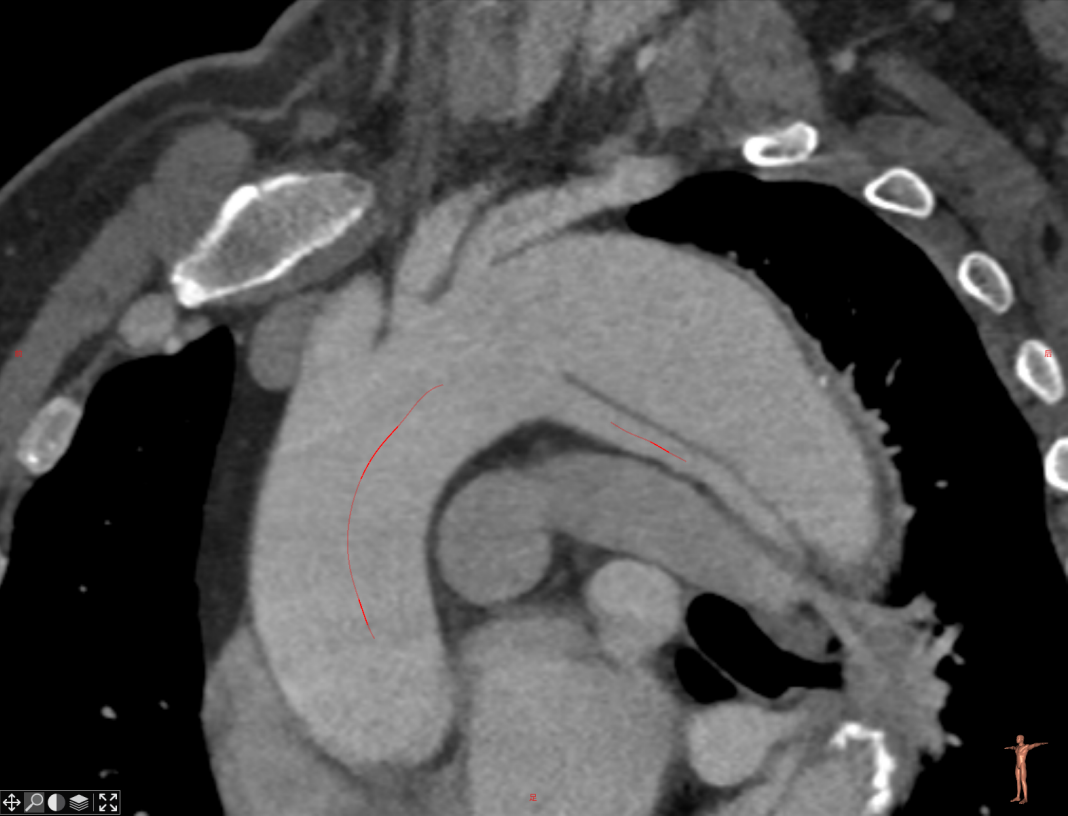

★ 病例1:主动脉弓夹层大裂口

★ 病例2:主动脉弓动脉瘤III型弓

III型弓,血管扭曲,LSA与主动脉呈锐角

术后造影无内漏,各分支形态良好,血流通畅